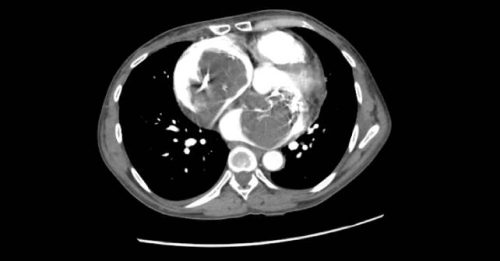

A 46-year-old female with a prior medical history of asthma presented to the emergency department with shortness…